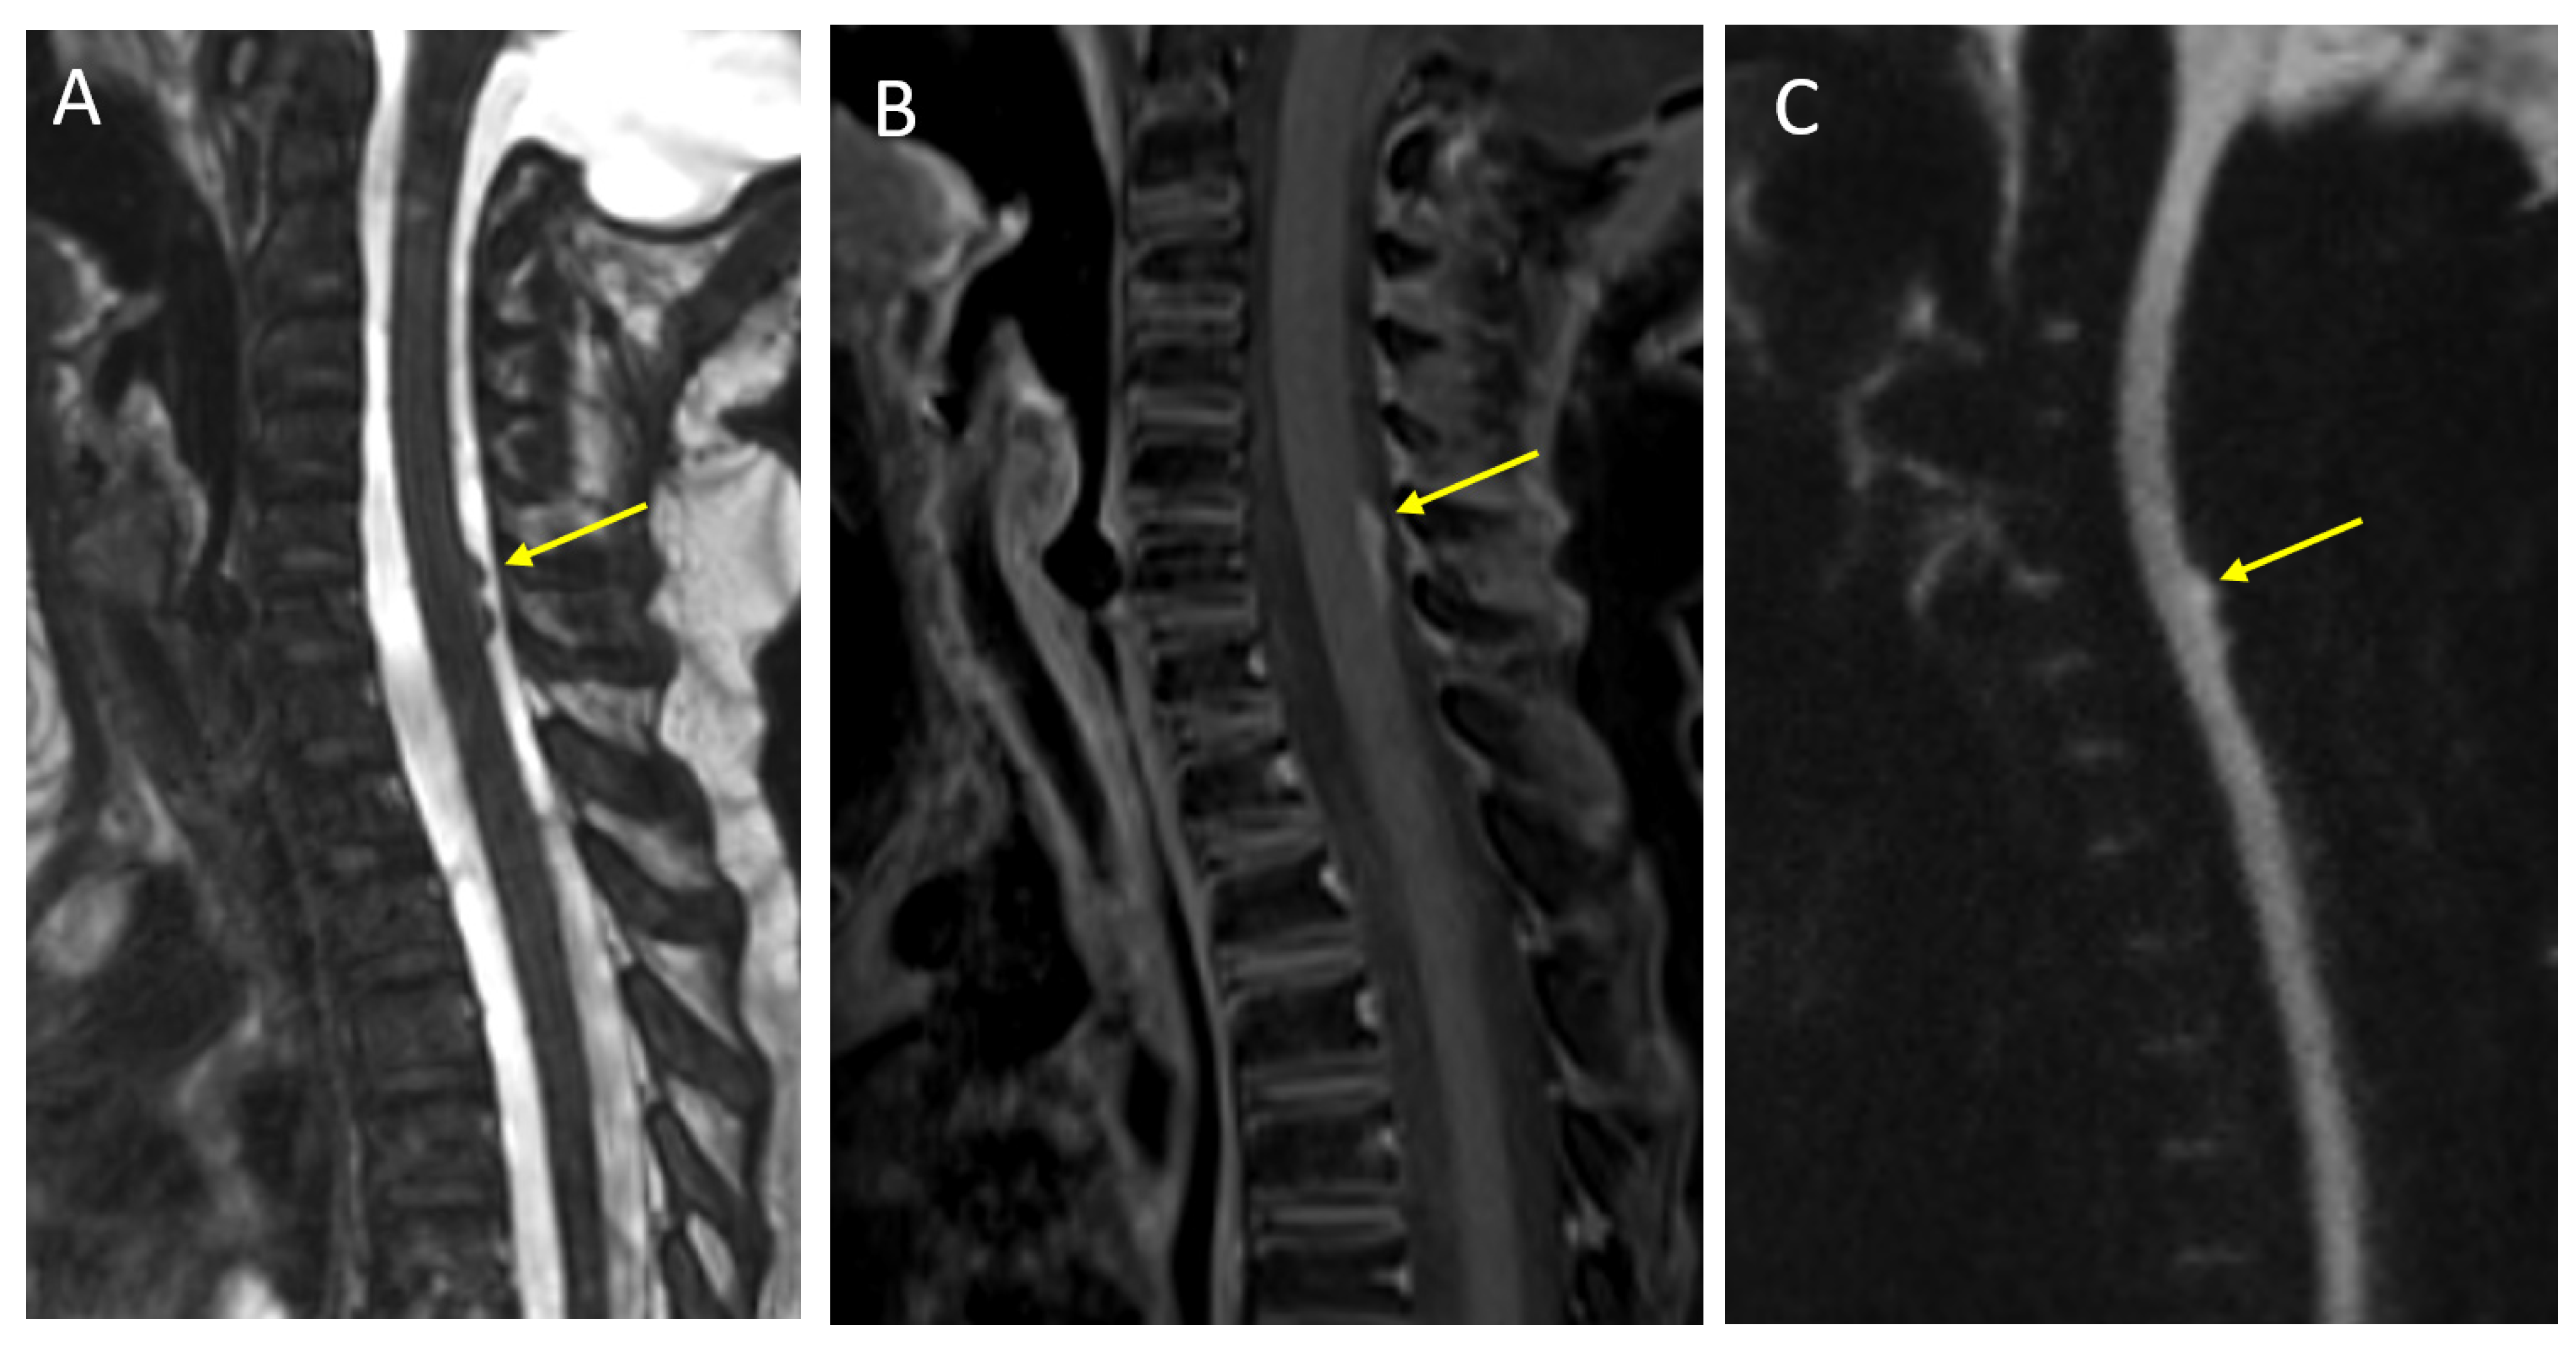

- Warren, K.E.; Vezina, G.; Poussaint, T.Y.; Warmuth-Metz, M.; Chamberlain, M.C.; Packer, R.J.; Brandes, A.A.; Reiss, M.; Goldman, S.; Fisher, M.J.; et al. Response assessment in medulloblastoma and leptomeningeal seeding tumors: Recommendations from the Response Assessment in Pediatric Neuro-Oncology committee. Neuro Oncol. 2018, 20, 13–23. [Google Scholar] [CrossRef]

- Hayes, L.L.; Jones, R.A.; Palasis, S.; Aguilera, D.; Porter, D.A. Drop metastases to the pediatric spine revealed with diffusion-weighted MR imaging. Pediatr. Radiol. 2012, 42, 1009–1013. [Google Scholar] [CrossRef]